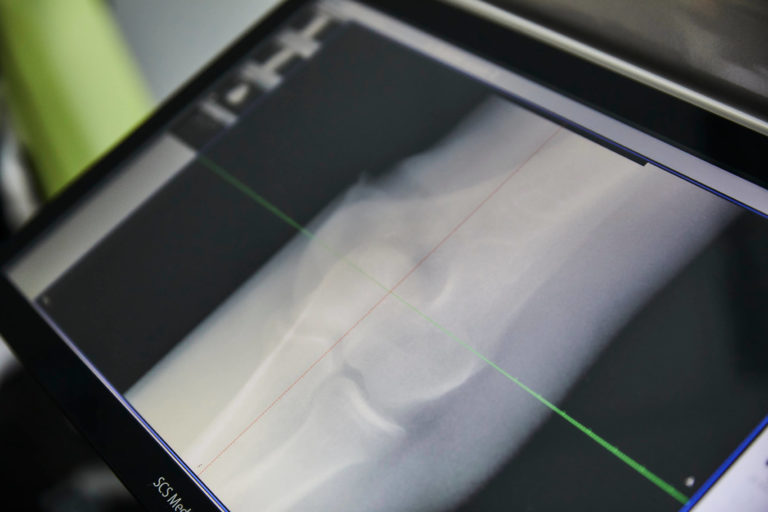

Um die Strahlungsbelastung für Sie aber so gering wie möglich zu halten, nutzen wir für Röntgenuntersuchungen die digitale Volumentomographie (DVT) und sind in Köln einer der ersten Anwender des SCS MedSeries® H22. Diese Technologie ist hochmodern und ermöglicht eine strahlungsärmere, präzise Diagnostik der Extremitäten.

Digitale Volumentomographie/DVT erkennt selbst feinste Brüche

DVT mit dem SCS MedSeries® H22 erzeugt direkt in unserer Praxis hochauflösende, dreidimensionale Bilder Ihres Körpers – und dies bei einer erstaunlich niedrigen Strahlendosis, die gerade mal ein Zehntel der Belastung von konventionellen Bildgebungssystemen mit sich bringt. Selbst feinste Brüche wie zum Beispiel an der Fußwurzel können mit dieser digitalen Volumentomographie unmittelbar vor Ort erkannt werden.

Mit der digitalen Volumentomographie werden die Bilder nicht mehr auf analogen Röntgenfilmen aufgenommen, sondern digital. So können sie jederzeit nachbearbeitet und überall abgerufen werden.